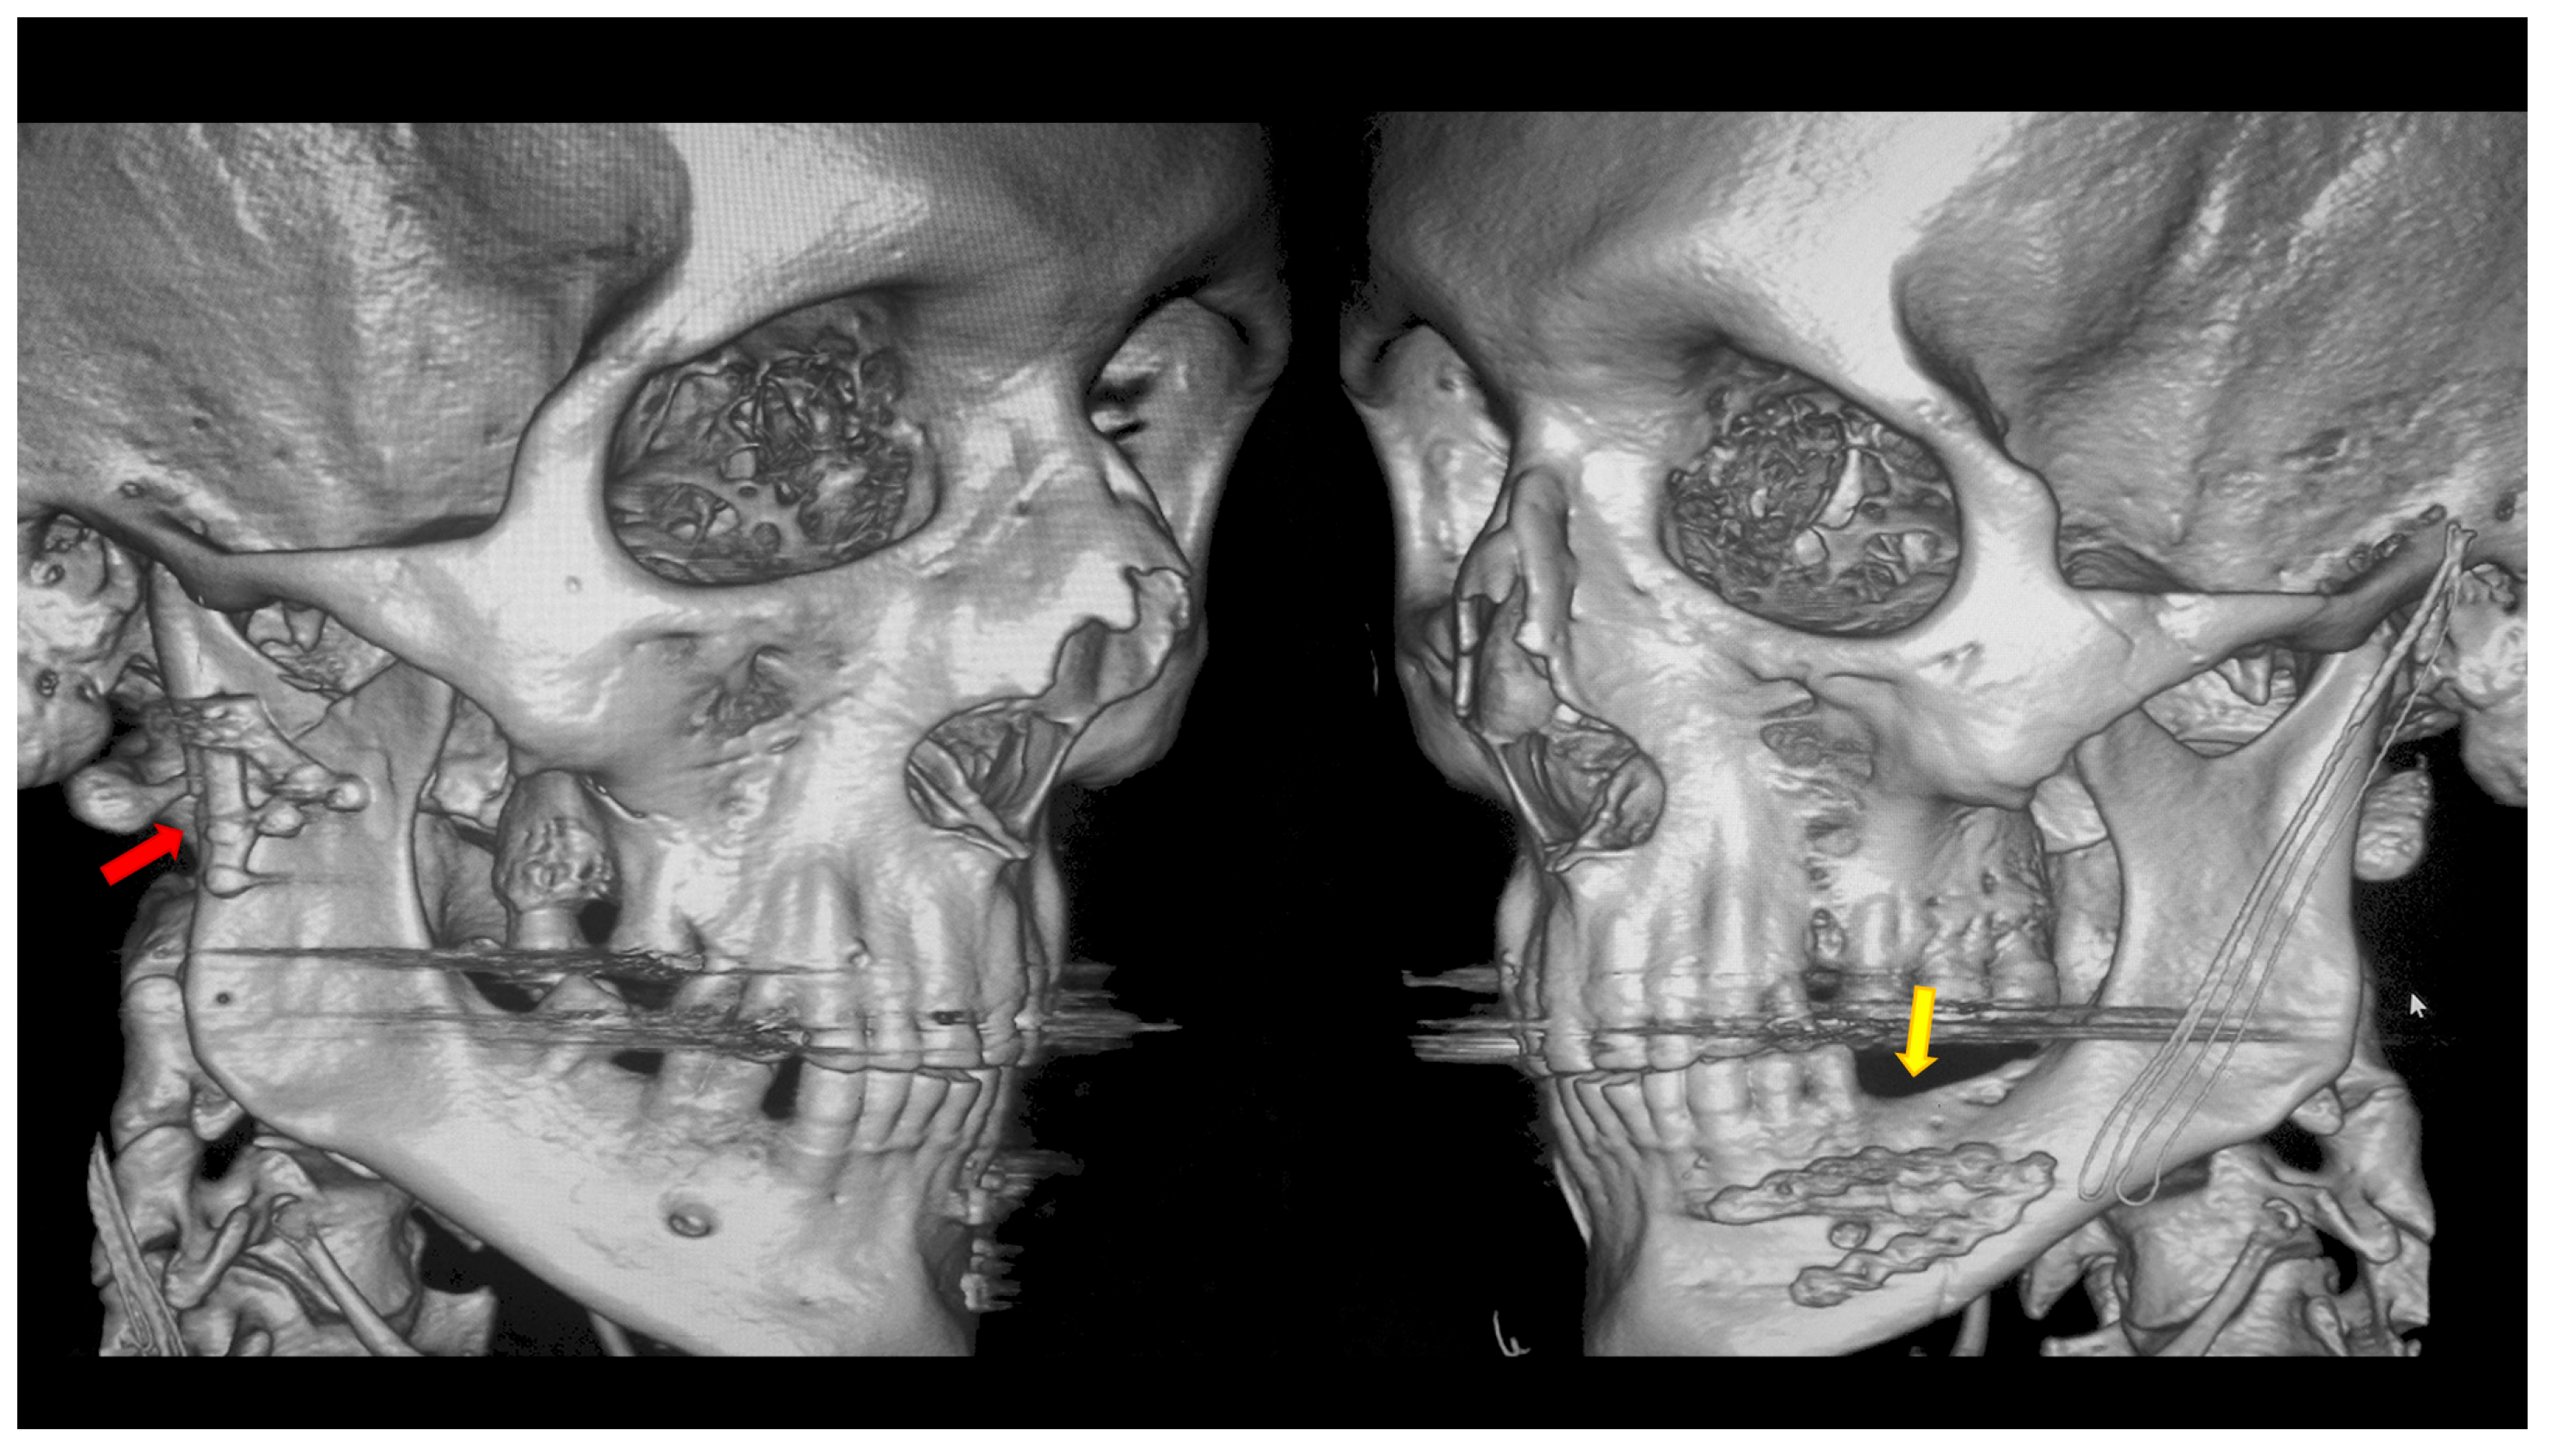

Figure 4.

Open rigid internal fixation was performed using a dedicated plate in the right condylar process (red arrow) and two straight plates of the 2.0 system on the left side of the mandibular body (yellow arrow).